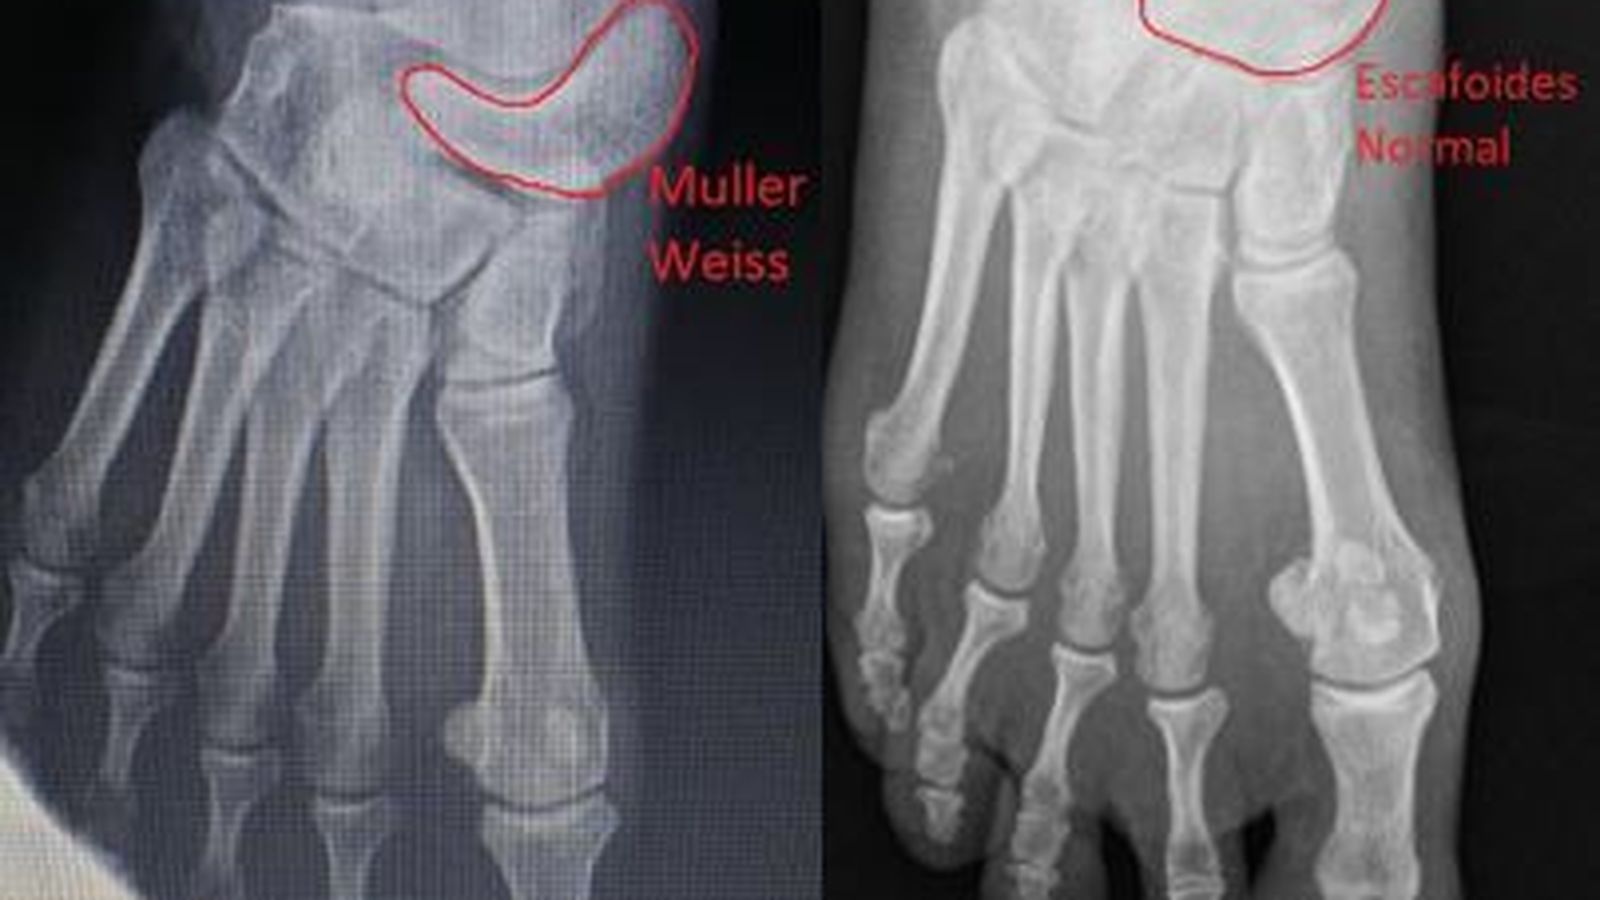

Comparación del escafoides con y sin síndrome de Müller-Weiss

Comparación del escafoides con y sin síndrome de Müller-Weiss / Doctor Iborra

El síndrome de Müller-Weiss, también conocido como osteocondritis del escafoides, es una deformidad de este hueso que se origina en la infancia pero no provoca síntomas hasta la edad adulta, por lo que es difícil de diagnosticar. Entre sus síntomas destaca el dolor agudo y crónico en la parte superior del pie y este puede ir acompañado de dolor o artritis en las rodillas. Las pruebas radiológicas o de resonancia magnética resultan fundamentales a la hora de localizarlo.